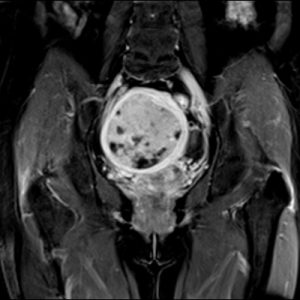

Chẩn đoán toàn thân: đầu, cổ, cột sống, khớp, bụng, tiểu khung, mạch máu